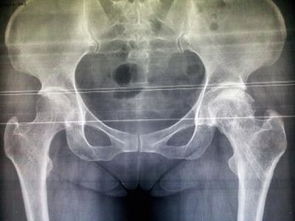

股骨頭壞死即股骨頭缺血性壞死,又稱無菌性股骨頭壞死。其癥狀是由于不同致病原因破壞了股骨頭的血液供應(yīng),因骨缺血而發(fā)生股骨頭骨質(zhì)壞死。 分型:股骨頭壞死的不同類型及壞死范圍和部位對治療方法的選擇起著重要的作用,因此我們結(jié)合X片、ECT及手術(shù)所見把股骨頭壞死分為以下四型、三級。

(1)缺血型。 (2)郁血型。 (3)混合型 (4)增生硬化型。